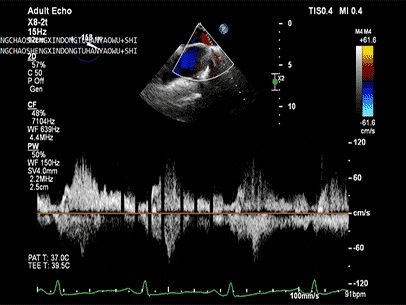

将MitraClip™XTR送入左房,由于左房太小,在达到骑跨过程中反复推进回撤CDS和稳定器,同时旋转SGC,达到骑跨的同时,保证Clip头端游离,且SGC在左房有深度。旋转M,同时顺时针往后旋转SGC借高度,使Clip垂直二尖瓣环平面,由于穿刺高度不够,Clip直接进入左室,这意味着操作要十分小心,左室组织复杂,稍有不慎将会造成组织损伤。使用A/P Konb中“A”旋钮借高度。确认垂直后,直接在左室打开Clip,3D外科视角,逆时针旋转使Clip夹臂处于11点-5点方向,回拉稳定器,使Clip处于3区脱垂区域,用“+/-”Knob中的“-”旋钮,使Clip更往后叶的同时增加操作高度,抓捕脱垂的瓣叶,关紧Clip后,反流从4+降低至0级,平均跨瓣压差2mmHg,左右肺静脉逆流均改善。前后叶活动度降低,后叶插入长度9mm,前叶插入12mm, 确认稳定性后释放Clip。释放后,即刻效果十分满意,手术圆满结束。